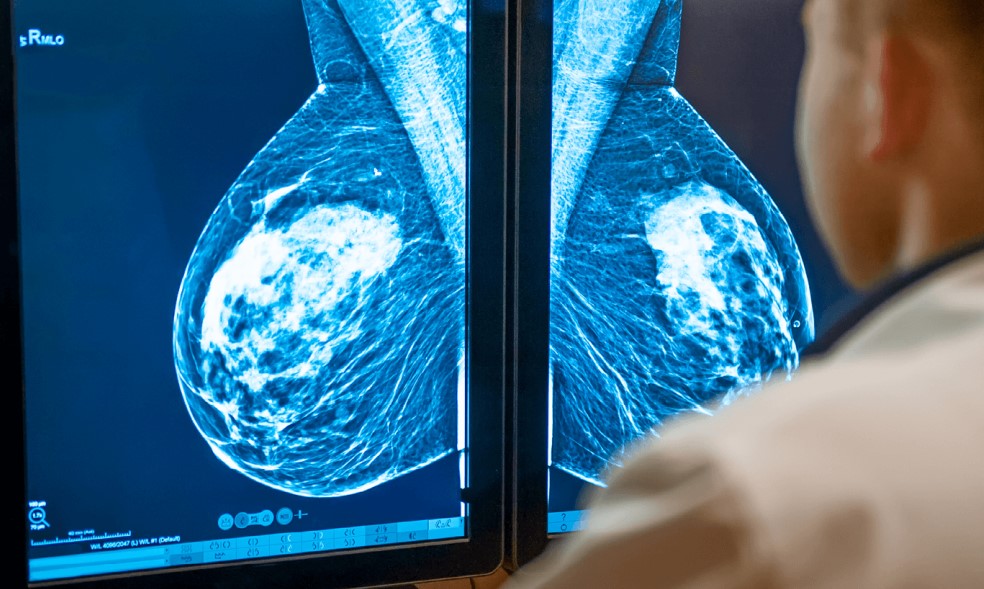

Plus de 50 caractéristiques mammaires identifiables

Grâce à des méthodes d'apprentissage profond (deep learning), Galen Breast a pu s'entraîner sur des centaines de milliers d'images pour identifier plus de 50 caractéristiques mammaires spécifiques. Durant l'étude, l'intelligence artificielle a analysé plus de 400 biopsies et les résultats ont été comparés aux diagnostics faits par deux pathologistes spécialistes du sein. Selon les résultats, l'IA était très précise et a pu distinguer avec précision plusieurs types de tumeurs, y compris des types rares. "J’ai eu le plaisir de participer à l’étude et à la validation de nouvelles innovations qui vont remodeler notre profession pour les années à venir, a déclaré Stuart Schnitt, chef du service de pathologie oncologique du sein au Dana-Farber/Brigham and Women’s Cancer Center et co-auteur de l’étude. J’ai hâte de voir d’autres applications de l’IA se généraliser dans l’utilisation clinique de routine à mesure qu’elles démontreront leur validité clinique."

Dans un communiqué, l'Institut Curie a taché à rappeler que le cancer de sein est le plus fréquent chez les femmes avec plus de 2,2 millions de nouveaux cas chaque année. Il est donc nécessaire d’obtenir des diagnostics plus rapides et plus fiable pour augmenter les chances de survie des patientes. Galen Breast a, donc, été créé pour remplir ces responsabilités. "En raison de l’augmentation de l’incidence globale du cancer du sein et de la diminution du nombre de pathologistes, la charge de travail imposée aux services de pathologie a considérablement augmenté, explique l’Institut Curie. Il existe donc un besoin croissant de solutions automatisées et d’outils d’aide à la décision."